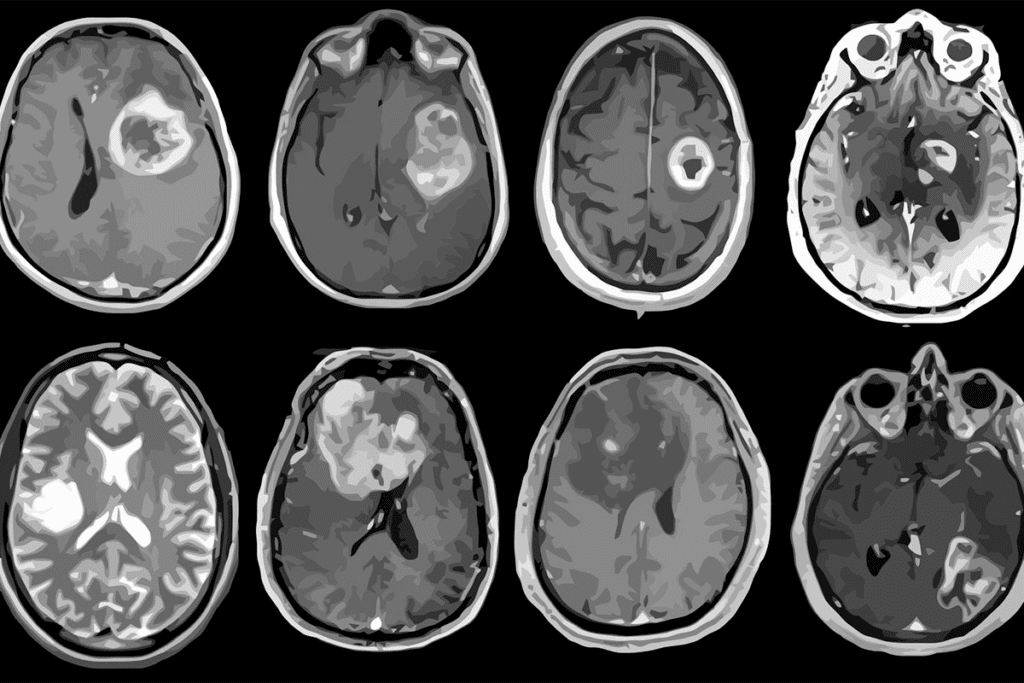

Types of Brain Tumors in Children

There are several kinds of brain tumors in kids, based on where they start and what they are like. Here are some of the most common ones:

- Medulloblastomas: These are the most common bad brain tumors in kids. They usually happen in the cerebellum.

- Glioma: Gliomas start from the brain’s glial tissue. They can be low-grade or high-grade.

- Ependymomas: These tumors grow from cells lining the ventricles and spinal cord’s central canal.

- Craniopharyngiomas: Even though they’re not cancerous, these tumors can harm a child’s health because of where they are.

Imaging Tests

Imaging tests are very important for diagnosing brain tumors in kids. The main tests are:

- Magnetic Resonance Imaging (MRI)

- Computed Tomography (CT) scans

- Positron Emission Tomography (PET) scans

These tests help doctors see the tumor, its size, and where it is. They also check how it affects the brain around it.